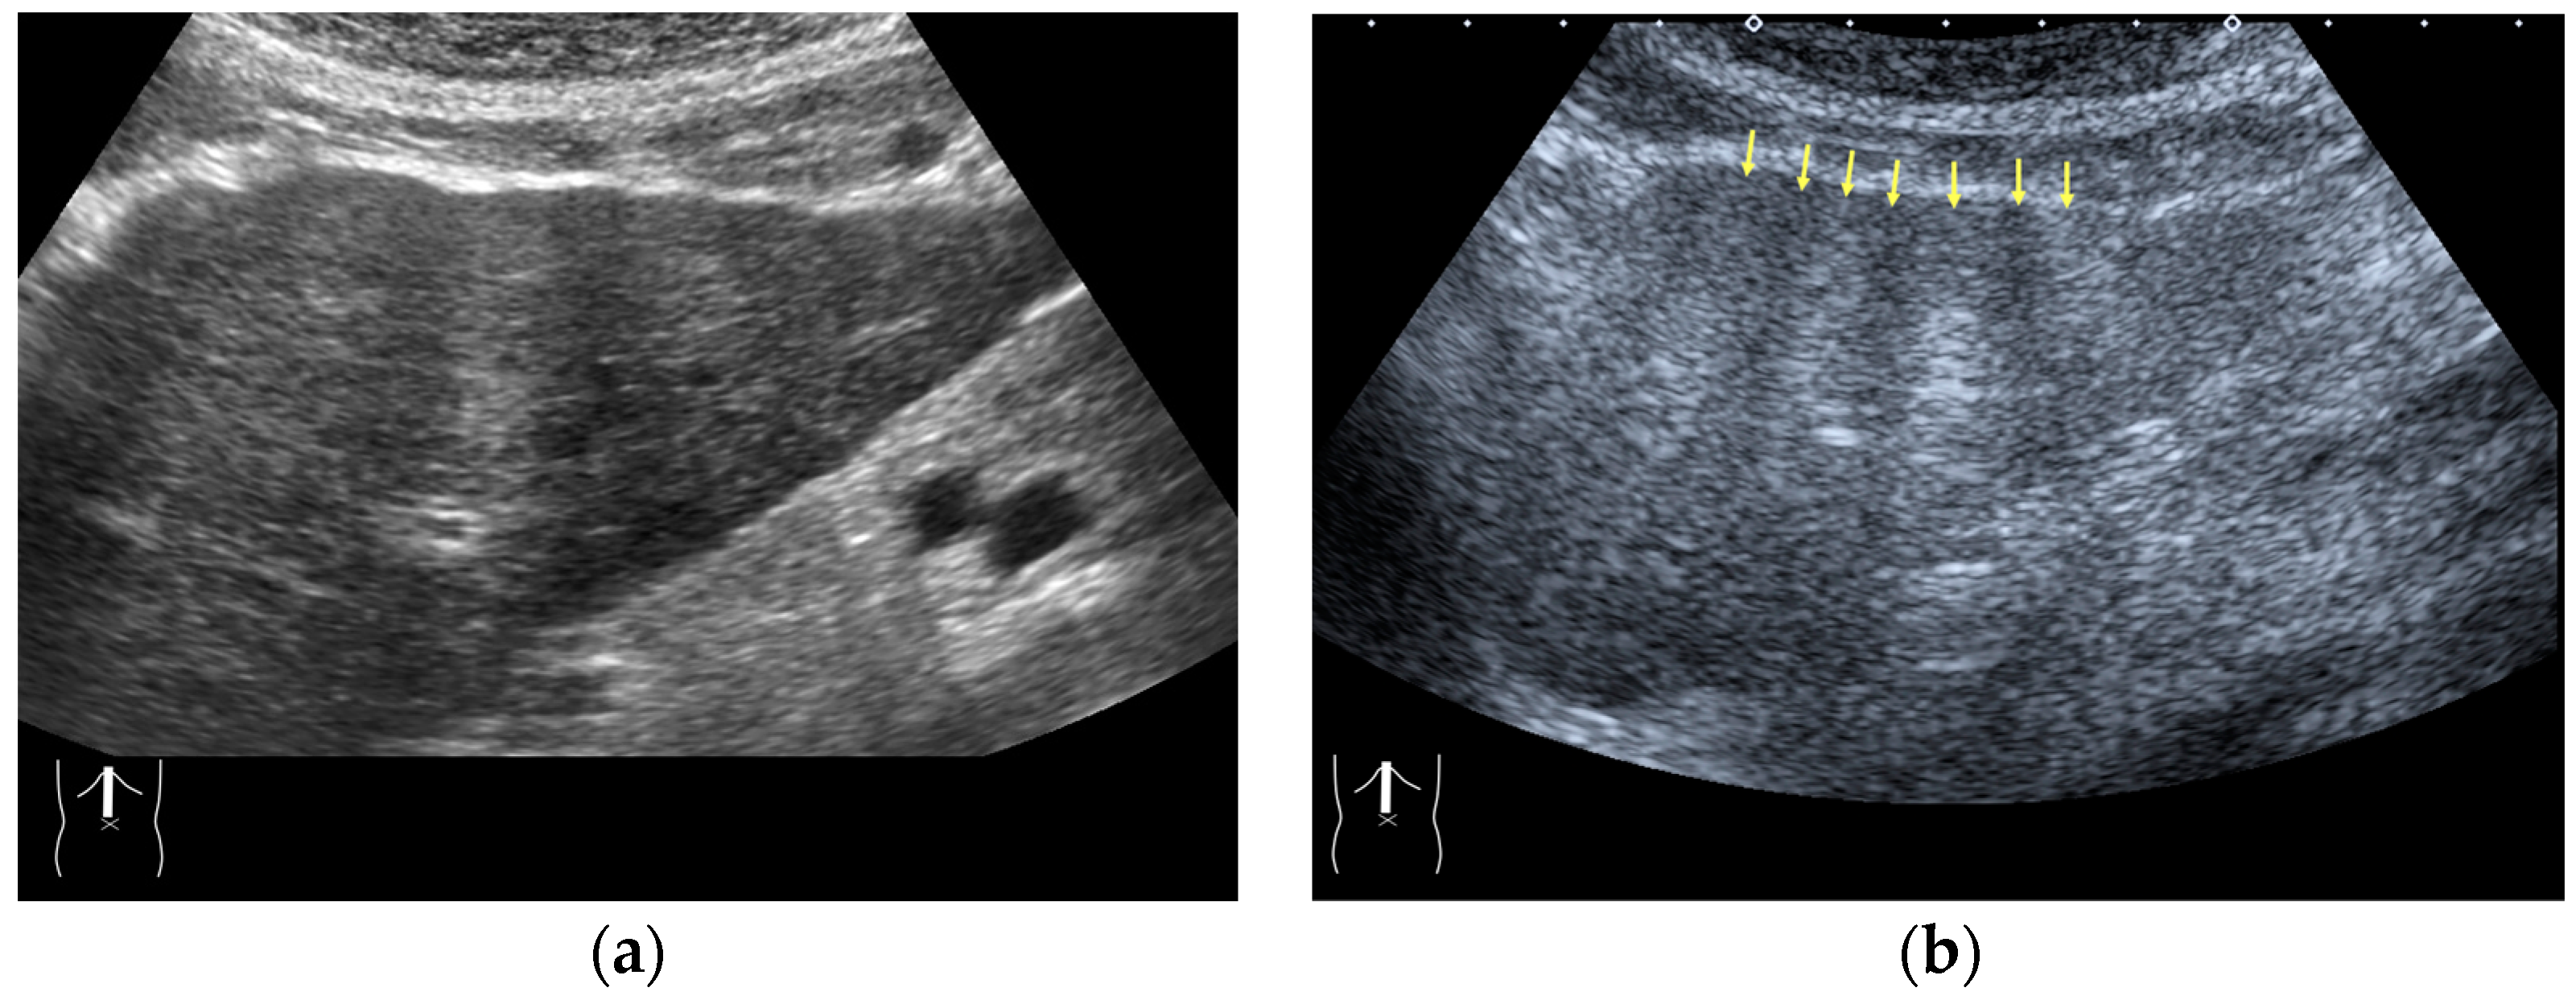

Figure 5.

Refraction artifact (3): hypoenhanced lines due to US refraction. (a) CEUS shows many hypoechoic lines throughout the liver parenchyma via transverse scanning (arrowheads). (b) The liver’s left lobe shows none of the lines seen in (a) via sagittal scanning. (c) A schematic drawing of sound refraction due to rectus abdominus via transverse scanning plane. The US beam changes direction twice, first at the surrounding tissue–rectus muscle interface, then at the rectus muscle–surrounding tissue interface.